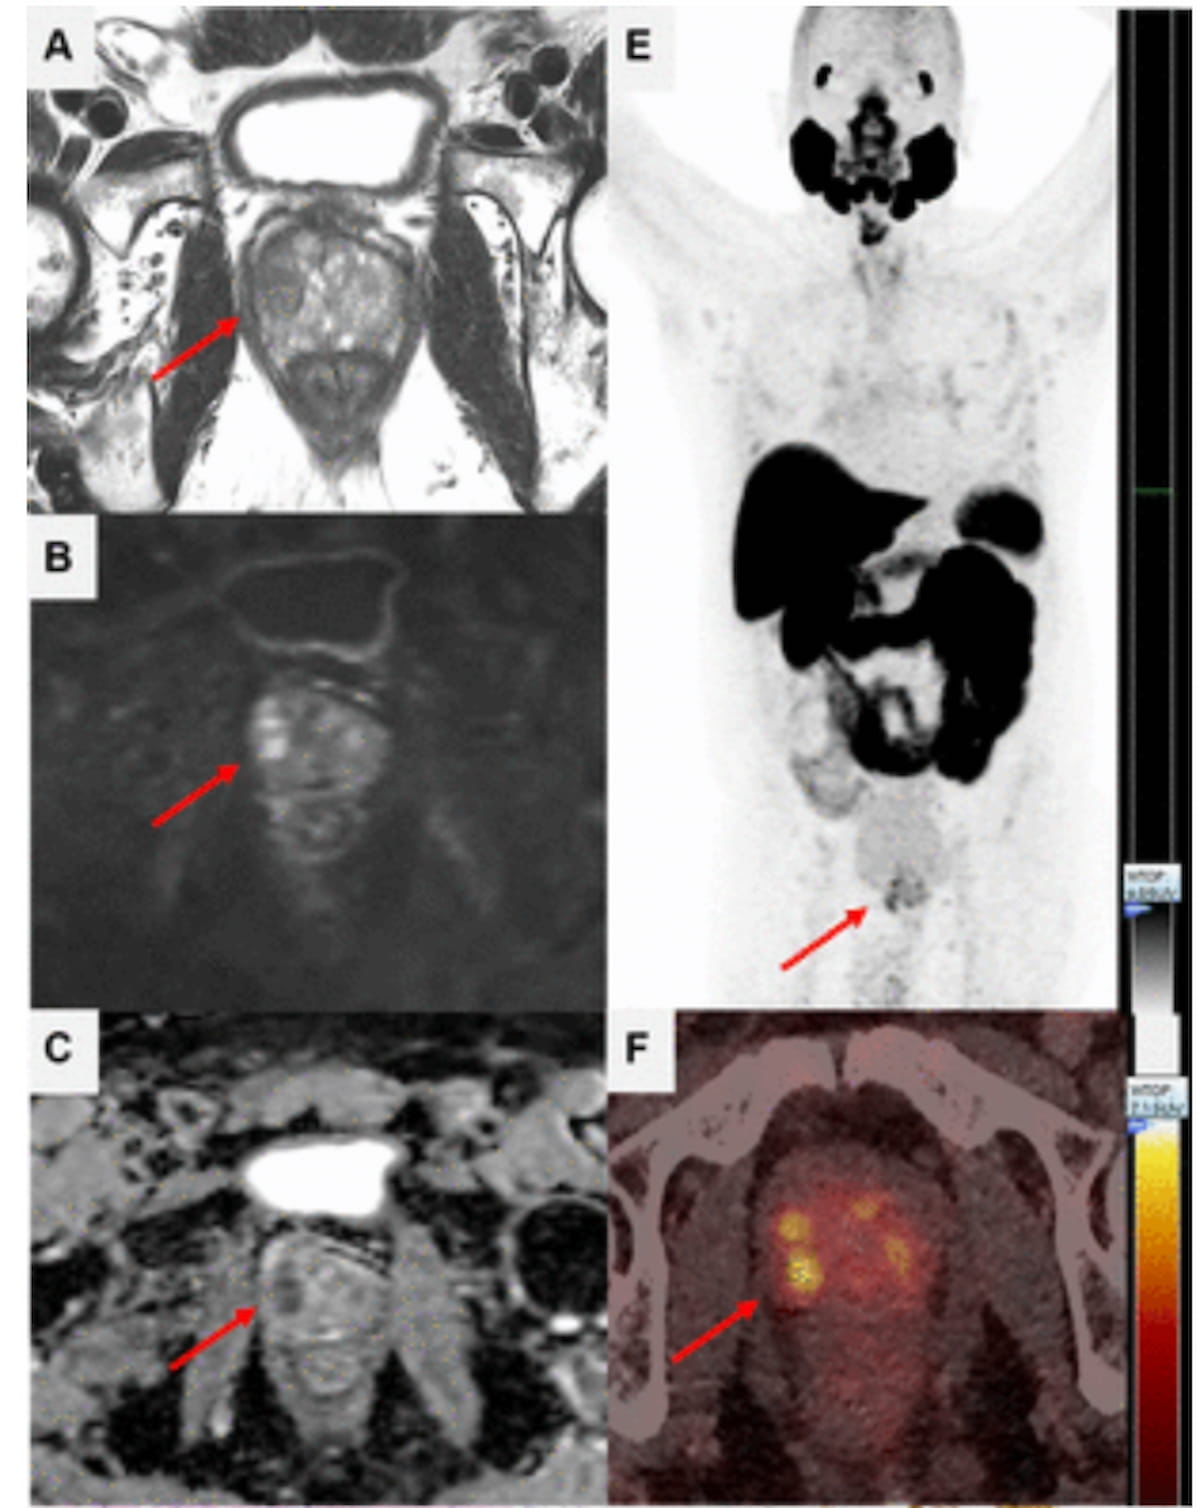

Sixty-five percent of patients with newly diagnosed high-risk prostate cancer may have extraprostatic extension on MRI, and PSMA PET/CT findings suggest those with Gleason scores of eight or higher have more than double the risk of metastasis, according to a new study presented at the European Congress of Radiology (ECR).